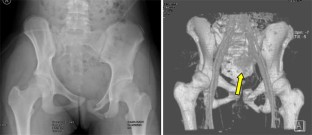

Abb. 5

Abb. 6

Abb. 7